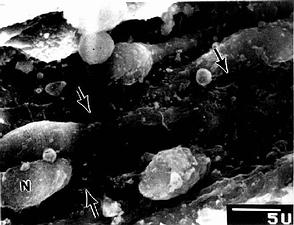

图9-22 大鼠脾血窦扫描电镜像

N内皮细胞核,↑内皮质间隙